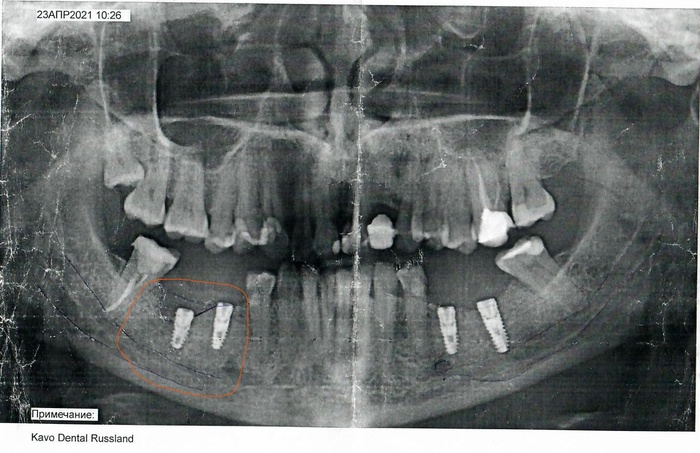

27 февраля 2021 года я решила окончательно удалить несчастные остатки 36 зуба, от него остались только стенки, и пошла в обычную районную поликлинику (Москва). Первый врач не взялся удалять, сказал зуб сложный, корень загнулся. Второй забацал укол и 40 минут пилил зуб на кусочки и вынимал их. В результате на месте зуба оказалась здоровая дыра. Как только она зажила, мне стало понятно, что с такими пустыми местами что-либо нормально жевать уже не получится и нужно ставить имплантаты. Почему не сделала раньше? А вот знаете, жевалось как-то и ладно. Но рано и поздно нужно было что-то делать. Решила сходить в районную стоматологию, так как частная была слишком дорогой и я, наивная, думала, что государственная поликлиника надёжнее в плане квалификации врачей. Записалась к врачу, у которого были хорошие отзывы и пошла. Врач, молодой мужчина лет 35, сразу стал уговаривать ставить имплантаты и назвал цену 4-х имплантатов. Говорил он это все на автомате и чувствовалось, что это он говорит это каждому пациенту, но не каждый, в районной то поликлинике, согласен на такие суммы. Я подумала, посоветовалось с родными, и решила заплатить и ходить с красивыми зубами. Сначала ставили винты слева. Не буду описывать весь процесс имплантации, таких описаний в инете куча. Я тряслась от страха, но оказалось, что врач действительно хороший. Он делал все исключительно ловко, быстро и напористо. Через минут 40 первая часть имплантации была закончена, мне установили винты слева. Все говорят, что самое сложное после окончания анестезии. Это, правда, болело адски. И, в общем, болело сильно дня 3, но через неделю от боли не осталось и следа, особенно когда сняли швы. И врач приступил к правой части. Именно там и была та здоровая дыра, которая оказалась после удаления сложного коренного зуба. 22 апреля, перед операцией я сделала рентген, и врач его видел. Он знал, что кость челюсти справа стала слишком узкой. Я виню себя, что не сказала ему об этом лишний раз. Фигурально выражаясь, я как Хаус не написала на ноге, не эта, а другая. Но так уж получилось…

И врач засадил мне в место удаленного зуба винт такой же длины, как и слева. Я чувствовала, что, несмотря на укол, мне больно и говорила ему об этом. Но он, может быть, подумал, что это мышцы болят от напряжения. Но, все-таки, заставил меня сразу после установки винтов сделать рентген. Я сидела в коридоре, а он все смотрел в кабинете на мой снимок и смотрел. Я поняла, что-то плохое случилось. Врач позвал меня, и сказала, что винт надавил на кость, и кость продавилась в канал, где находится нижнечелюстной нерв. И что велика вероятность, что после окончания анестезии, у меня будет онемение правой стороны лица в районе губы и подбородка. С тяжестью в душе я пошла домой, и стала ждать, что будет. Анестезия прошла, но онемение нет. Я вообще не чувствовала губу справа, подбородок справа, зубы с 31 по 34 и десну под ними, онемела (немного) правая сторона языка. В панике я позвонила врачу, он успокоил меня, как мог и сказал приходить на следующий день.

23 апреля он вывернул установленный на месте 36 зуба винт и поставил другой, короче.